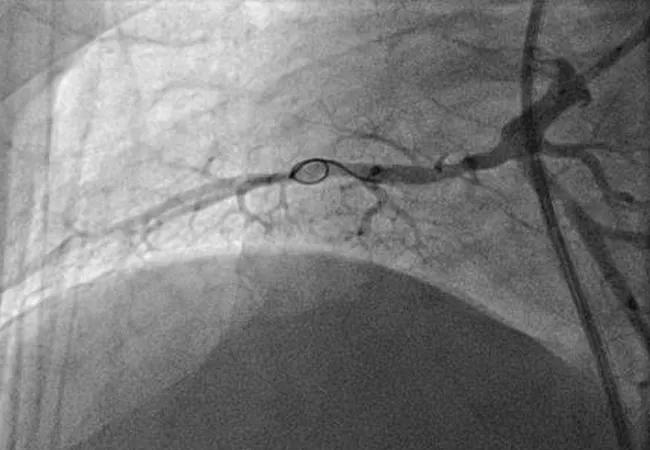

Figures. Imaging studies of the right lower lobe in one of the Cleveland Clinic CTEPH cases before (top), during (middle) and after (bottom) successful balloon pulmonary angioplasty.

Dr. Shishehbor treated each patient “without any complications and with immediate radiographic improvement in pulmonary blood flow,” says Dr. Heresi-Davila, Medical Director of the Pulmonary Thromboendarterectomy Program in Cleveland Clinic’s Department of Pulmonary and Critical Care Medicine.